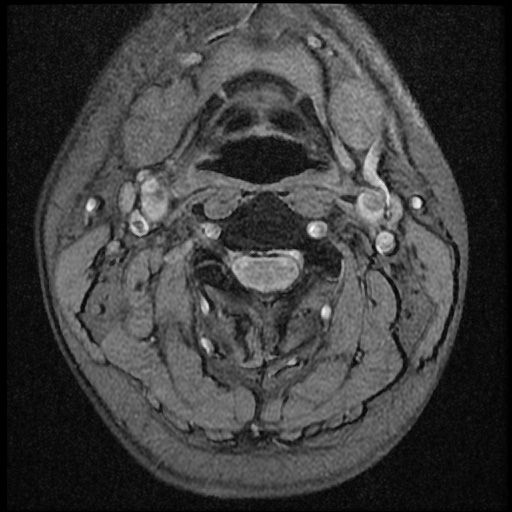

이 MRI 사진은 21년도 사고 당시 찍은 MRI 사진 입니다. 확인 부탁드립니다~

전체 mri를 다 봐여겠지만 보여주신 mri 컷에서는 의미있는 경추 디스크탈출이 보이지 않습니다.